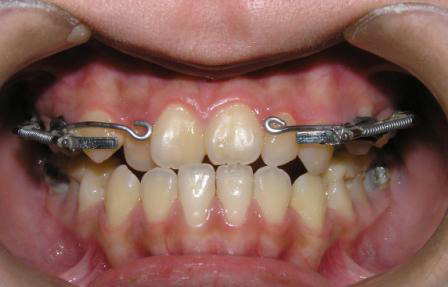

1、牙列拥挤

由于牙量大于骨量,造成牙齿畸形,因此,正畸治疗可利用拔牙后产生的间隙重新排齐拥挤的牙齿,从而协调牙量与骨量的关系,减少畸形复发。

2、牙齿前突

如前牙过于前突的人群,就需要拔掉一定数量的牙,以获得间隙,达到内收前牙、前移后牙的目的,缓解面部前突,从而使得顾客的面部侧貌更美观。

3、矫正咬合关系异常

牙齿咬合异常者,可通过拔牙正畸治疗调节上下牙的咬合关系。拔牙间隙调整后牙咬合关系,使得后牙尖窝交错,咬合接触面积最大,达到最佳的咀嚼效率。